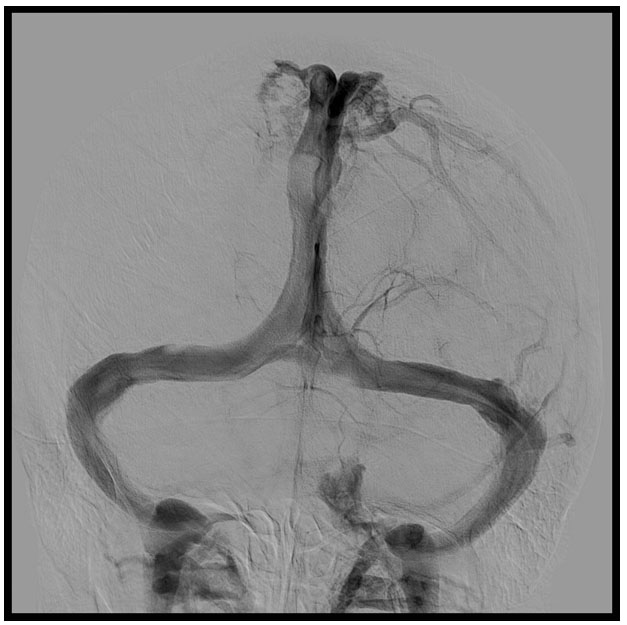

On the other hand, an anatomical variant was observed: the right Labbé vein was hypoplastic, with compensatory hypertrophy of Trolard vein. This finding could explain the intensity of the symptoms presented in the patient (Figure 4).

Figure 4: Venography showing right Labbé vein hypoplastic, with compensatory hypertrophy of Trolard vein.

Share Image:

In our case, the right Labbé vein was hypoplastic, with compensatory hypertrophy of Trolard vein, explaining the symptoms with the partial stenosis of the superior sagittal sinus (Figure 4).